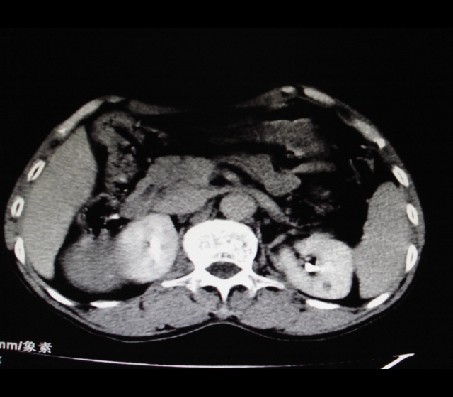

男性,68岁。b超发现肝右叶占位,afp27(正常小于20),+c后三期如下:

快进快出,典型肝癌表现,可见假包膜延迟强化

1、支持肝右叶巨块型肝癌   2、左肾小囊肿。

表现典型,可能为纤维板型。介入治疗效果不错,尔后可以再做射频、亚氦刀或手术,并结合生物治疗效果更佳。

典型的原发性肝癌,部分外生。

1)肝右叶巨块型肝癌(部分外生)。2)左肾小囊肿。